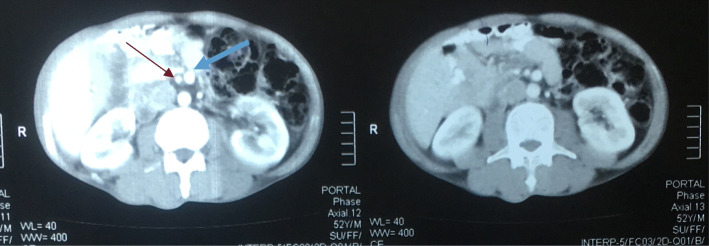

Fig. 2.

Computed tomographic scan of the abdomen showing inversion of superior mesenteric artery (red arrow) and superior mesenteric vein (blue arrow)